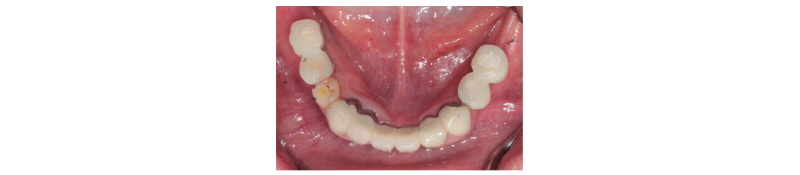

Fig. 25. Intraoral photo taken before surgery. |

Ju Whan Lee : Computer-guided Flapless Implant Surgery and Immediate Loading with Customized Restoration, Comparing and Reviewing Error of Guided Surgery. Implantology 2017 |

본 59세 여환은 양쪽 위, 아래 큰 어금니가 흔들리고 잇몸이 부었으며 왼쪽 아래 큰 어금니는 오랫동안 없었다는 주소로 본원에 내원하여 임상 및 방사선학적 검진 결과 아래와 같이 관찰되었다. #33 치아는 Mob (+++) Per (+)와 bone loss, #16, 26, 46 치아는 Mob (++/+++) Per (+)와 bone loss, #36, 37 치아는 missing 상태였다. 이에 #16, 26, 33, 46 치아는 hopeless teeth, #17, 36, 37, 47 치아는 missing teeth로 진단되었다(Fig. 19). #16, 26, 33, 46 치아는 발치 후, #i16, i17, i26, i33, i36, i37, i46, i47에 implant 식립과 #i16, i17, i26에 sinus lifting 및 #i33, i46, i47에 GBR을 계획하였다. #i36, i37은 flapless implant surgery 및 immediate loading을 계획하였다. #16, 26, 33, 46 치아를 발치하였고, 2개월 후에, 상, 하 rubber impression 채득 후, stone model 제작하였다. 또한 arch 전용 tray를 bite한 상태로(Fig. 20, 21) CBCT 촬영을 하였다(PHT-30LFO, VATECH). 이후 CBCT 영상과 alveolar ridge와 soft tissue model을 scanning한 영상(TRANSFORMER, Megagen)을 정합하였다. 새로운 영상을 바탕으로 #i36, i37 위치에 implant fixture 식립과 customized abutment와 provisional bridge를 design하였다(R2GATETM, Megagen, Fig. 22, 23). Design대로 3D printer (Perfactory Digital Dental Printer 3, EnvisionTEC) 통해 surgical guide를 제작하였고(Fig. 24) milling machine (TicamPro and WhitecamPro, Megagen)으로 customized abutment와 provisional bridge를 milling하였다(Fig. 28). 임플란트 수술은 5회에 걸쳐서 진행하기로 하였다. 첫 번째 수술일에는 #i36, i37 fixture 식립과 동시에 abutment 체결과 provisional bridge를 합착하였다(Fig. 25-27, 29). 이후, 1개월 후에 #i16, i17 fixture 식립과 lateral approach로써 sinus lifting을 시술하였다. 3개월 후에 #i36, i37에 최종 인상 채득하여 도재금관 수복을 하였다(Fig. 30, 31). 향후 남은 부위에 임플란트 수술 및 보철 진행 예정이다.